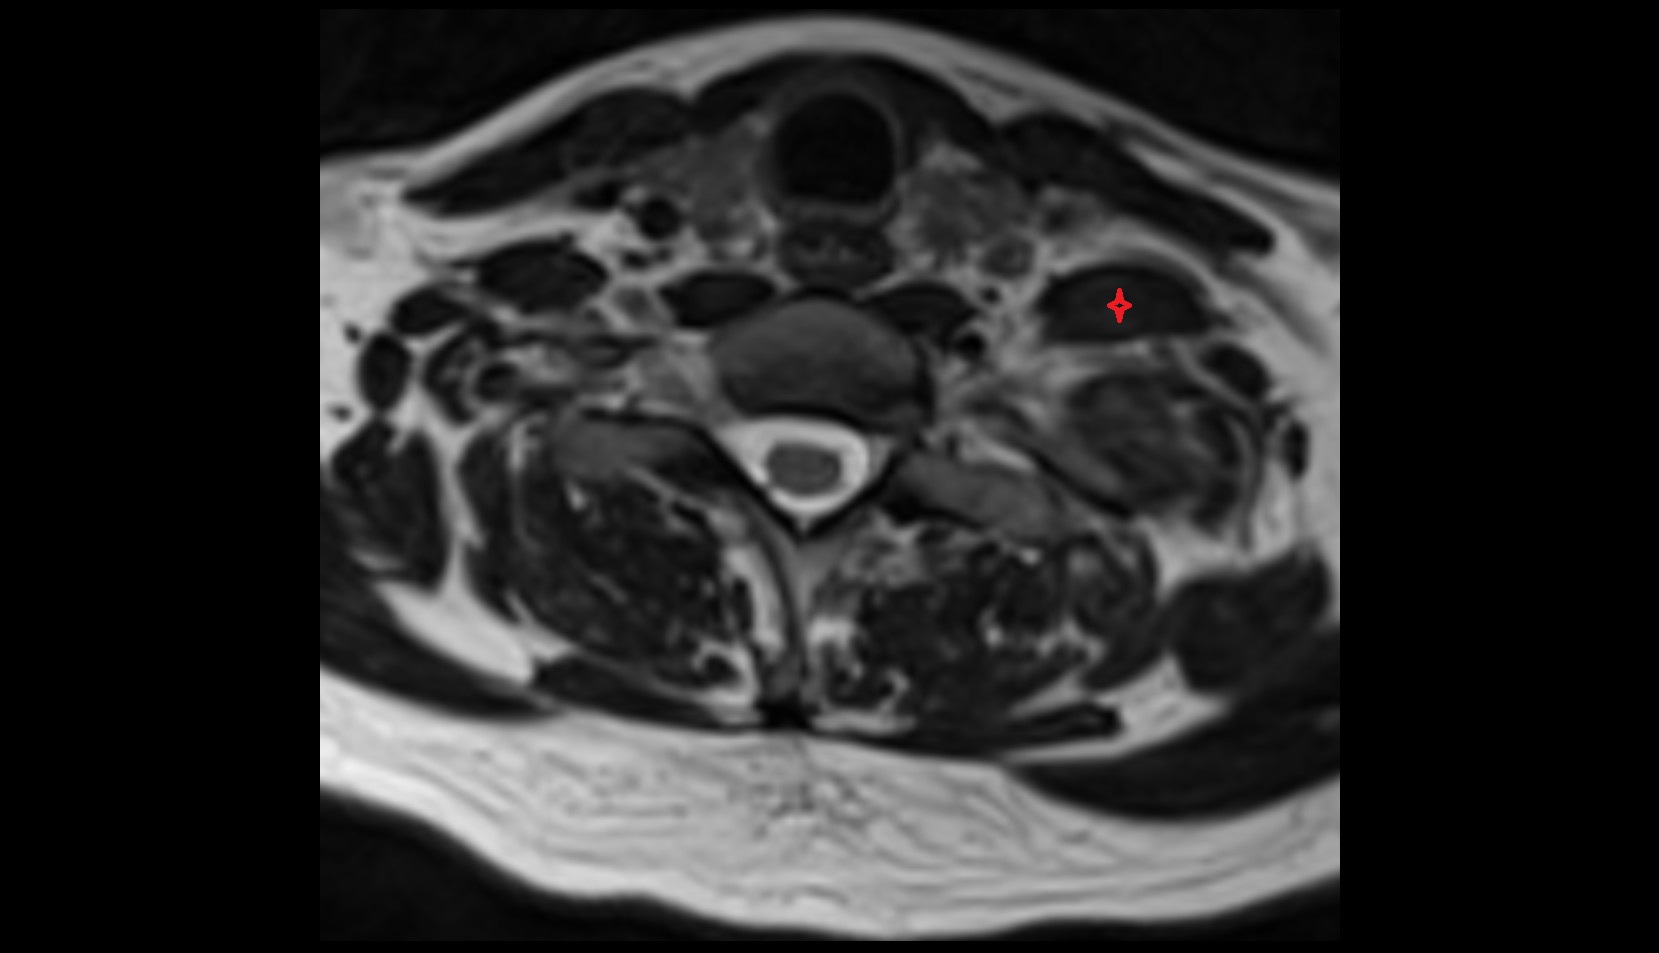

- Peripheral zone of prostate

- Anterior Fibromuscular Stroma of prostate

- Central zone of prostate

- Transitional zone of prostate